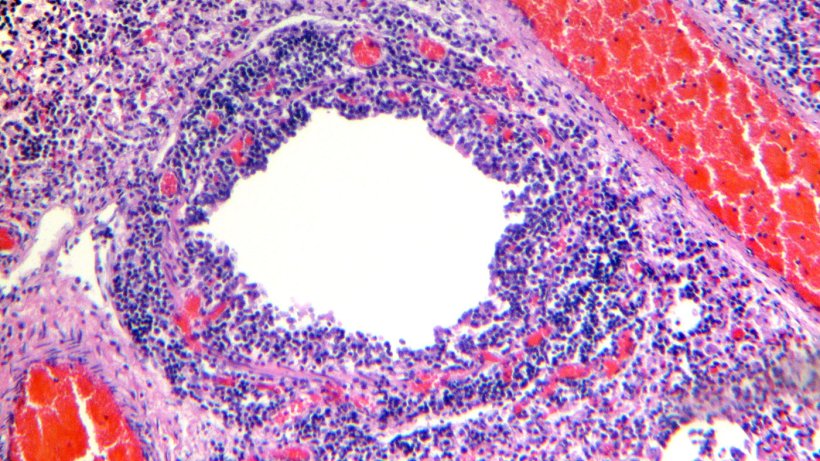

Examen histologique du tissu pulmonaire montrant une infiltration lymphocytaire de la lamina propria et de la sous-muqueuse bronchique (Figures 4 et 5).

Figure 5. Infiltrat de lymphocytes périvasculaires.